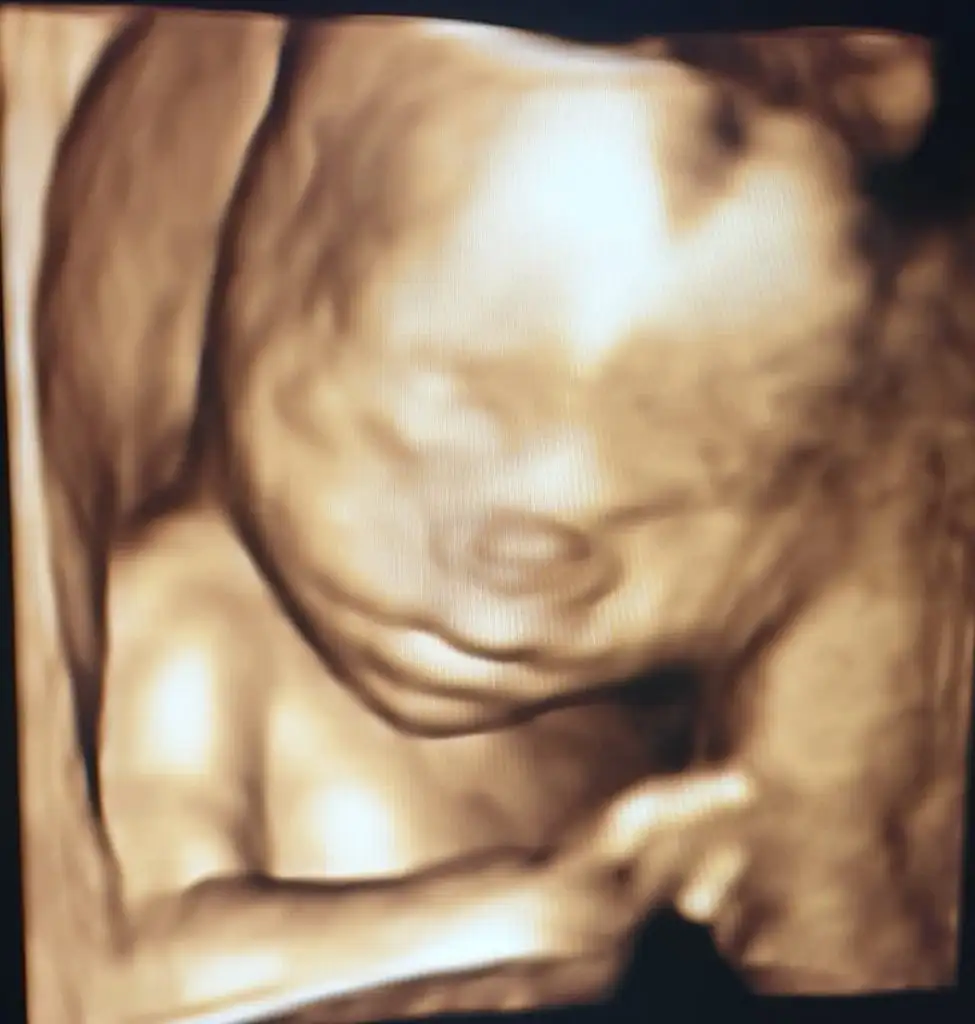

Güzel dilekleriniz için teşekkür ederim. Doktordan geldim ben. Herşey yolunda çok şükür çok sağlıklı bebeğim

Yarım saat sürdü. Sata göre 20+6 yım ultrasonda 21+5 çıktı. 424 gram, 24.5 cm boyunca bir kızçem var

Eli hep yüzündeydi fotolarda ama bir kaç tane alabildik. Ekliyorum♥